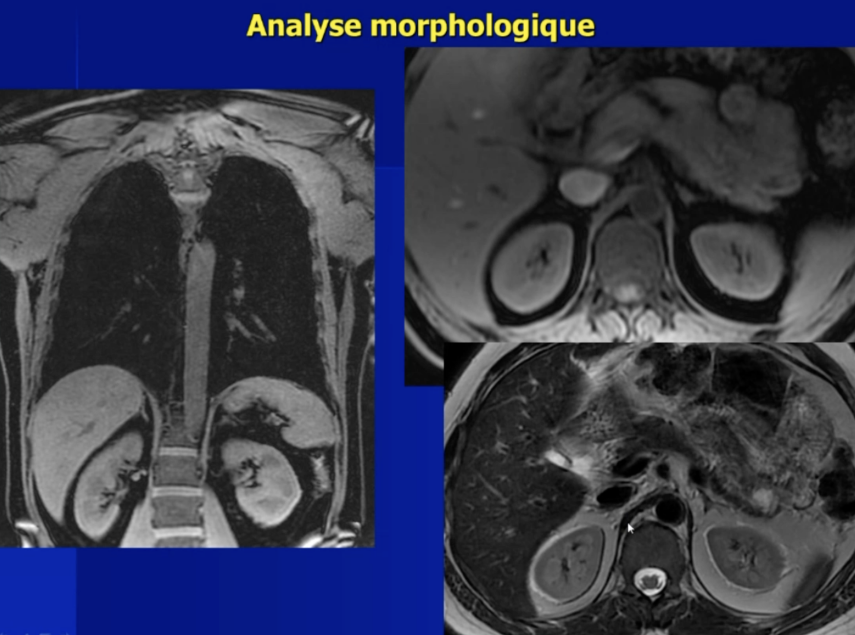

Evaluation Fonctionnelle par IRM

Analyse Morphologique en T1FS et T2

- Piliers du diaphragme

- Trophicité / Epaisseur du diaphragme